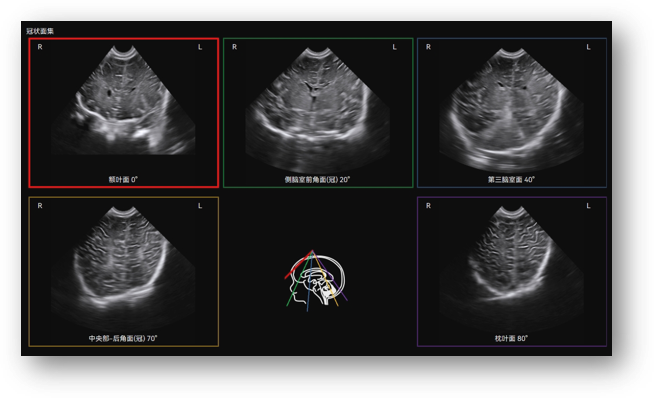

Craniocerebral Ultrasound Tomography (Infant) automatically identifies the 12 standard craniocerebral sections of the pediatric brain through volume data